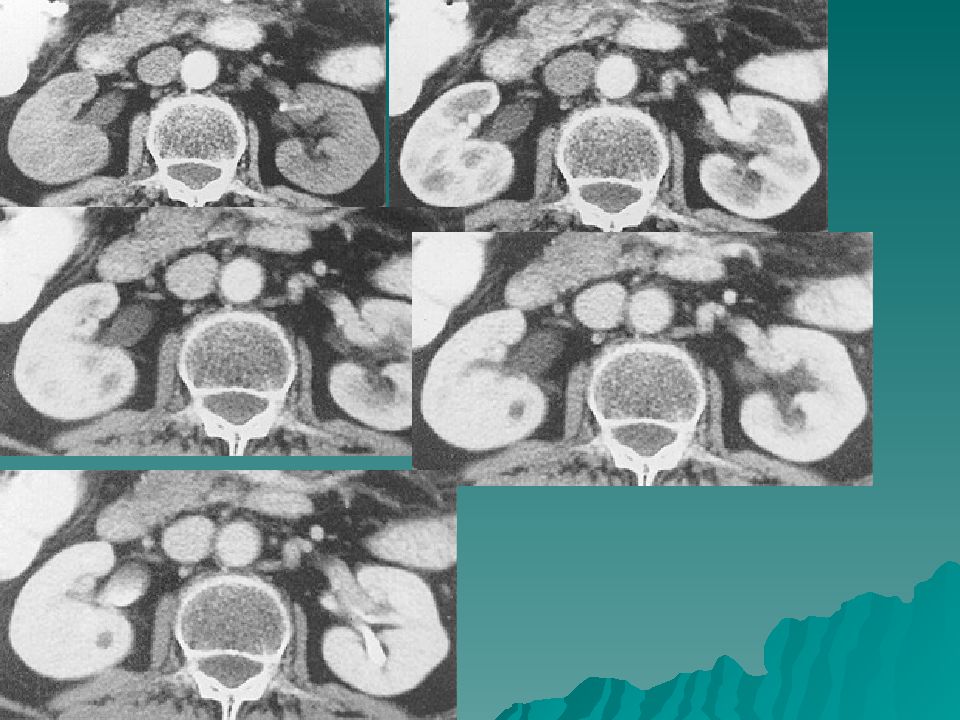

Интраренальная лоханка: рентгеновские снимки и примеры